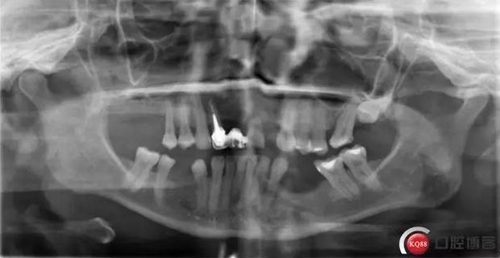

種植體和下頜頦神經“近距離接觸”一例 科貿嘉友收錄

看了黃生醫(yī)生的 “一例避開下齒槽神經管種植病例 “ 一文, 想起自己有一例植體靠近下頜頦孔的病例。找出來和大家分享一下。

術前